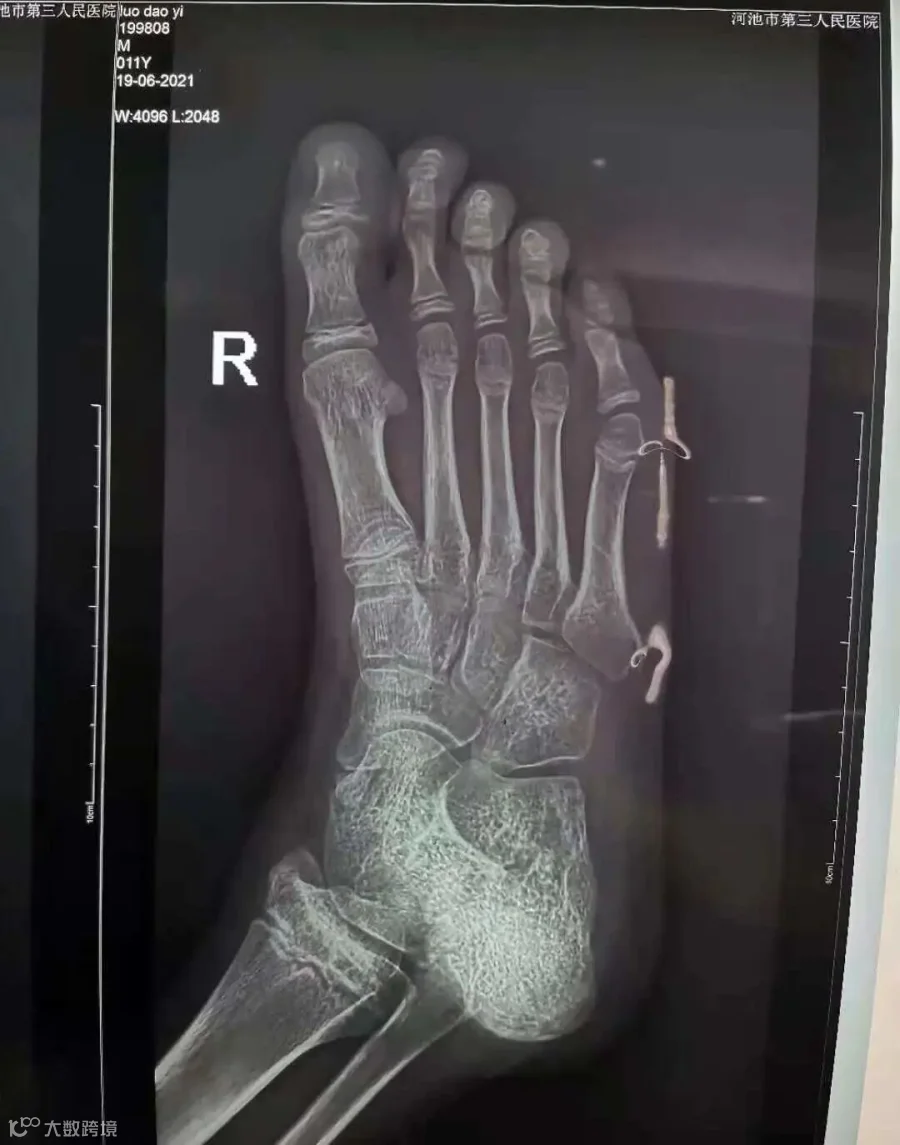

罗云(化名),11岁4月

治疗后